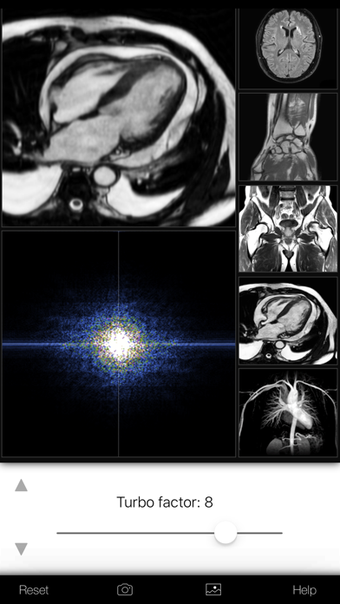

Een volledige versie app voor iPhone, door Eltjo Haselhoff.

A K-Space Odysseyis een app met volledige versie voor iPhone, die deel uitmaakt van de categorie ' Geneeskunde'.

Over A K-Space Odyssey voor iPhone

Een K-Space Odyssey is beschikbaar voor iOS 12.1.2 of hoger. De huidige versie van de software is 1.9.1 en u kunt deze alleen in het Engels krijgen.